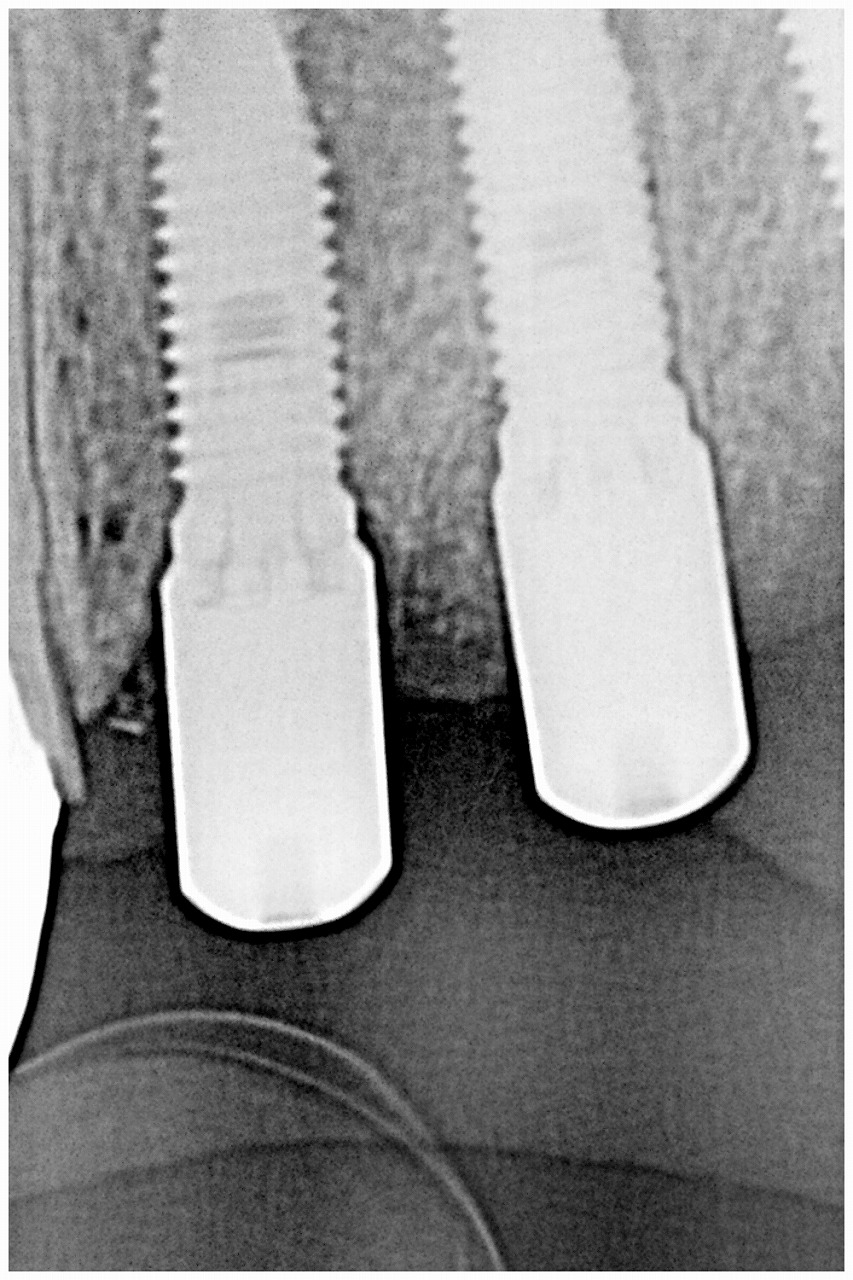

抜歯即時インプラント埋入から狩場の下で2か月半固まるのを

待ちました

最小限で歯肉の成形をしています

このように固まりました

問題ありません